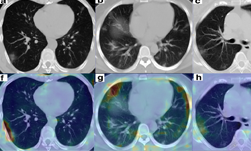

This work encompassed two models that were used in series to come up with the COVID final classification model. The first model was a segmentation model that was used to define the lung regions which were subsequently used by the classification model. Initially, they developed two classification models — one utilizing the entire lung region with fixed input size (full 3D), and one utilizing average score of multiple regions within each lung at fixed image resolution (hybrid 3D).

Training converged at highest validation accuracy of 92.4% and 91.7% for hybrid 3D and full 3D classification models, respectively, for the task determining COVID-19 vs. other conditions. The validation accuracy in an unseen independent test set was observed with the 3D classification model (93.9%), with resultant probability of COVID-19 disease demonstrating 0.941 AUC. This was the model that was selected at the end, and published on NVIDIA NGC.